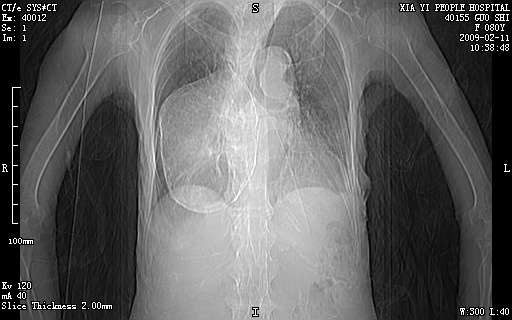

以下是引用随光逐影在2009-2-16 16:34:00的发言:[br]1)考虑右前纵隔皮样囊肿。2)双侧少量胸腔积液。

以下是引用zjzjr在2009-2-16 17:30:00的发言:[br]支持囊性畸胎瘤 双侧少量胸腔积液。